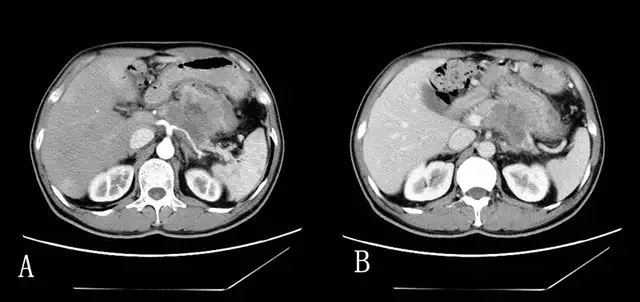

那篇登上顶级期刊封面的论文,配图正是恩师的CT影像与AI的识别结果。